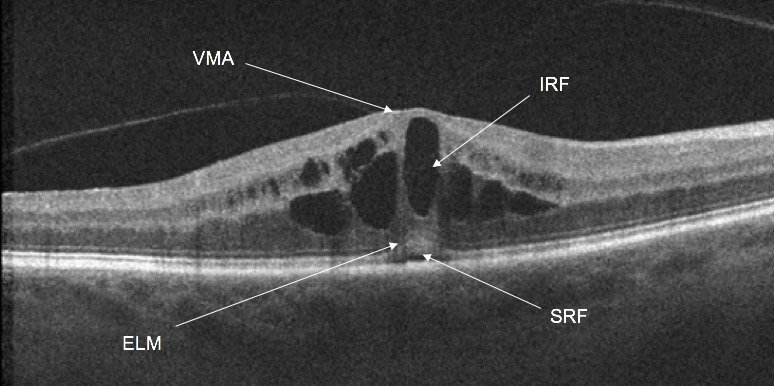

This patient lost their vision after an MVA. Why?

In this image there is evidence of vitreomacular adhesion. In the center of the image, there is intraretinal fluid in the inner nuclear layer and at the junction between the outer plexiform/nuclear layer. There is also some subretinal fluid. The patient’s angiogram demonstrates a petaloid pattern (video). The ellipsoid is a little thickened centrally.

This patient was diagnosed with whiplash maculopathy.